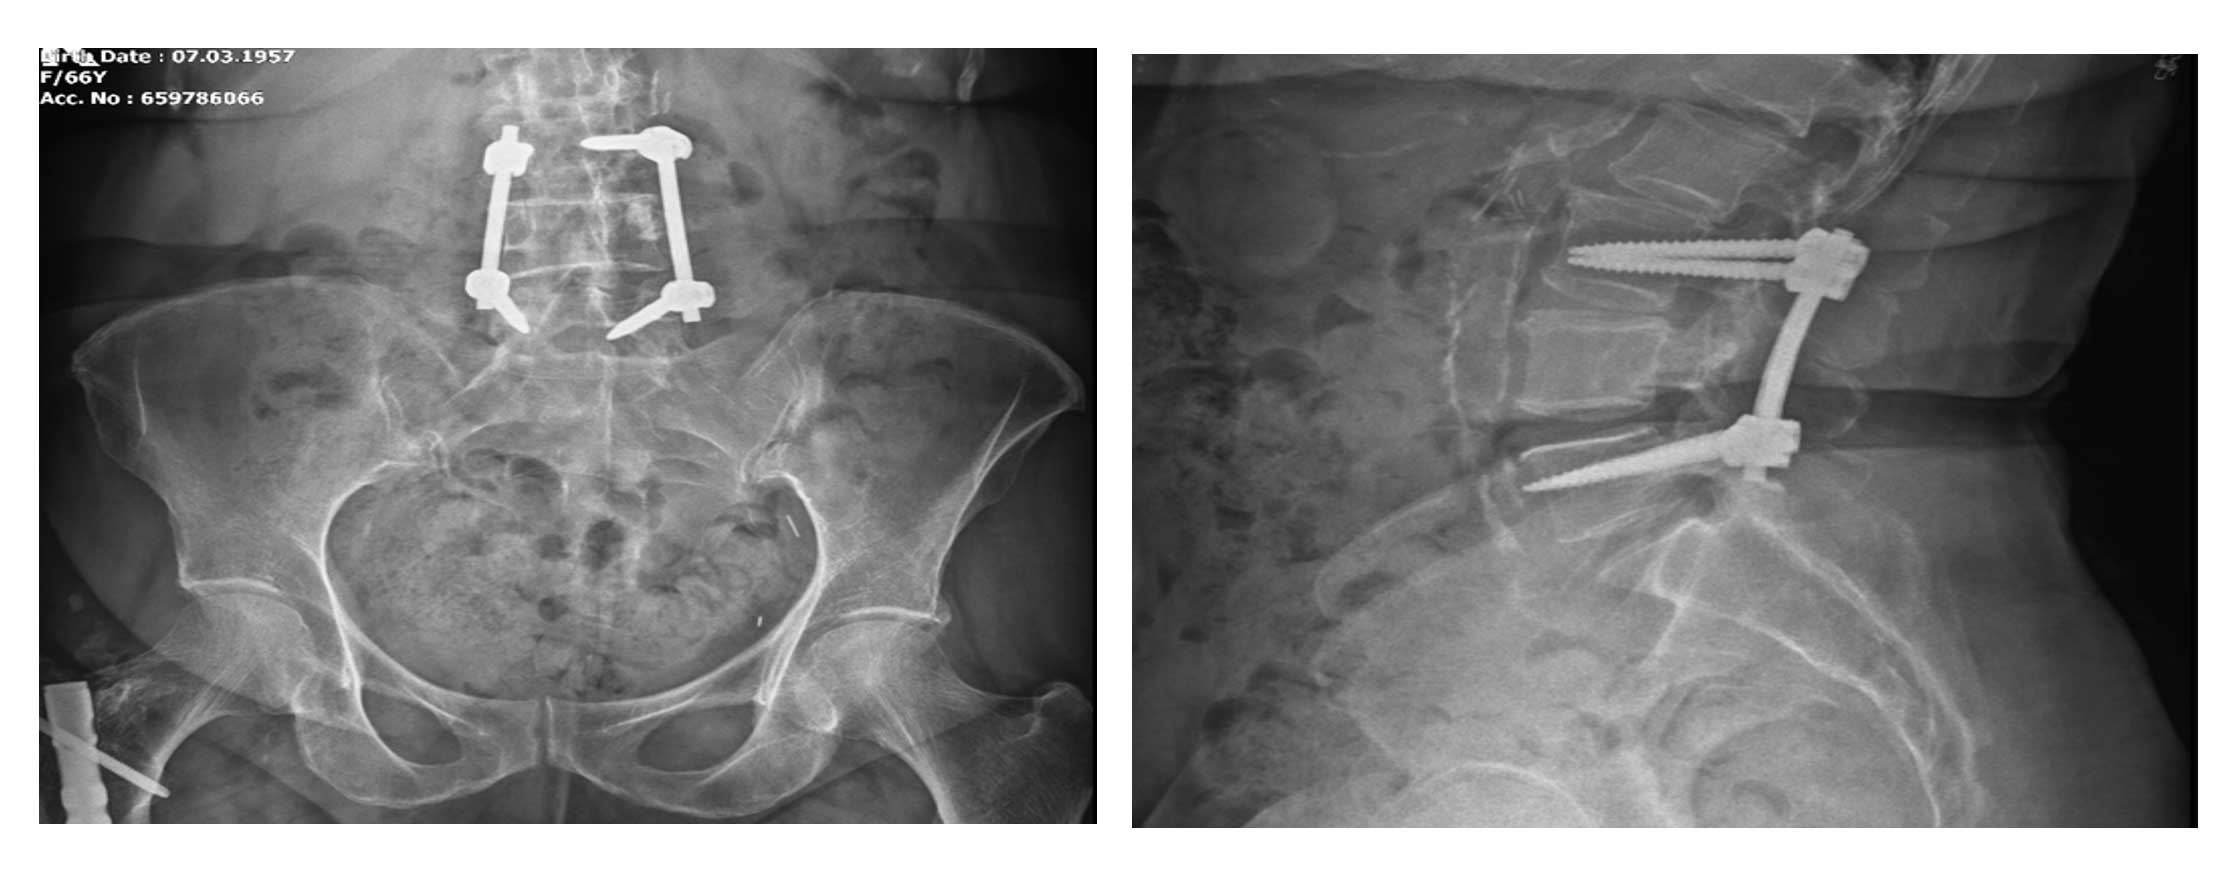

Ameliyat Öncesi: Röntgende L4 vertebrada yeniklik, bir alt ve üst vertebrada vidalama görülmekte